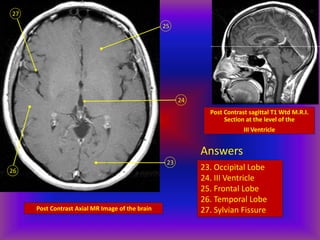

Post Contrast Axial MR Image of the brain

23

24

25

26

27

Post Contrast sagittal T1 Wtd M.R.I.

Section at the level of the

III Ventricle

Answers

23. Occipital Lobe

24. III Ventricle

25. Frontal Lobe

26. Temporal Lobe

27. Sylvian Fissure